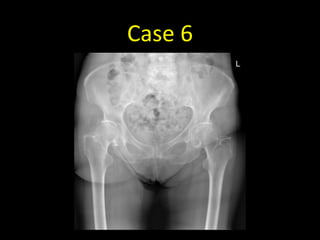

Case 6

• 87 year old with pain in the hip after a fall out of bed

• AP radiograph of the pelvis in

an 86 year old female

• There is a linear non-

displaced fracture of the right

femoral neck